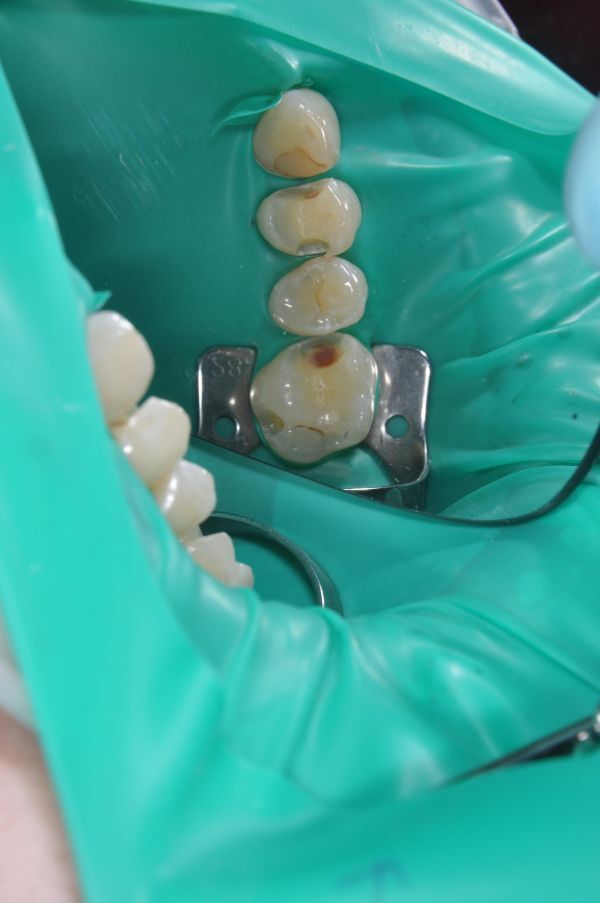

• Изоляция зуба от слюны и влажного дыхания пациента. Качество композитной реставрации зубов ухудшается, поскольку влага отрицательно влияет на пломбы из фотополимерных материалов. При нарушении техники изоляции могут проявиться такие нежелательные последствия¸ как выпадение пломбы либо нарушение краевого прилегания и развитие вторичного кариеса.

• Моделирование коронки зуба. Для прямой реставрации зубов применяются композиты светового отверждения. Материалы различных оттенков наносятся послойно, благодаря чему удается добиться необходимого цвета, формы, а кроме того, снизить полимеризационную усадку пломбы.